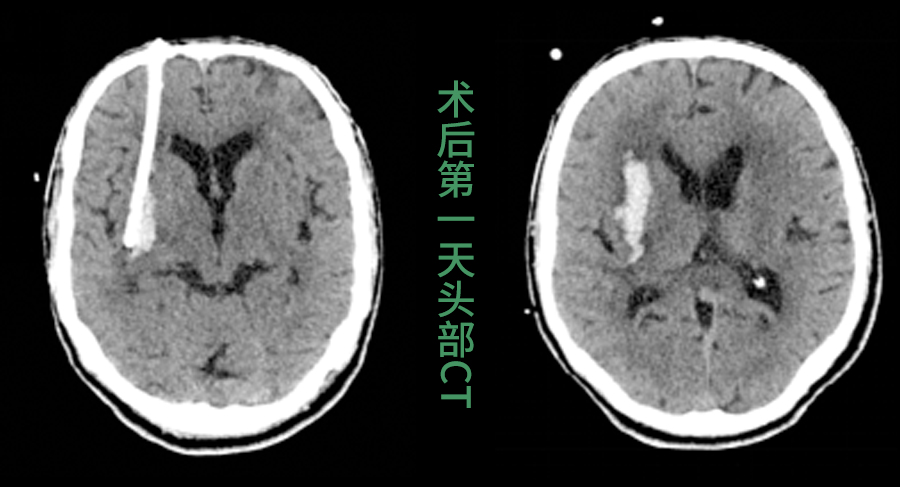

3.精准引导,一击即中:手术中,这枚特殊的“GPS”导板稳固贴合在患者头部,为手术穿刺针提供精确的进针角度和深度通道,穿刺导管沿此通道进入,直达血肿中心,实现毫米级的精准定位。